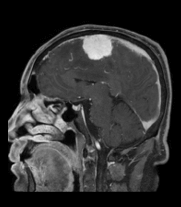

- 脳を包んでいる髄膜と呼ばれる膜の細胞からできてくる腫瘍で、脳そのものを圧迫するように大きくなります。原発性脳腫瘍の代表的なものの一つで、女性に多い腫瘍で、ほとんどは良性です。また、多発することもあります。最近は脳ドックの普及で無症状であるにもかかわらず、偶然みつかることも多くなりました。

- CTやMRIなどで造影剤を使用した診断が行われます。特にMRIが有効で、頭蓋底部に発生した小さな髄膜腫の診断にも優れています。時に脳の血管を直接写す、脳血管撮影が行われます。